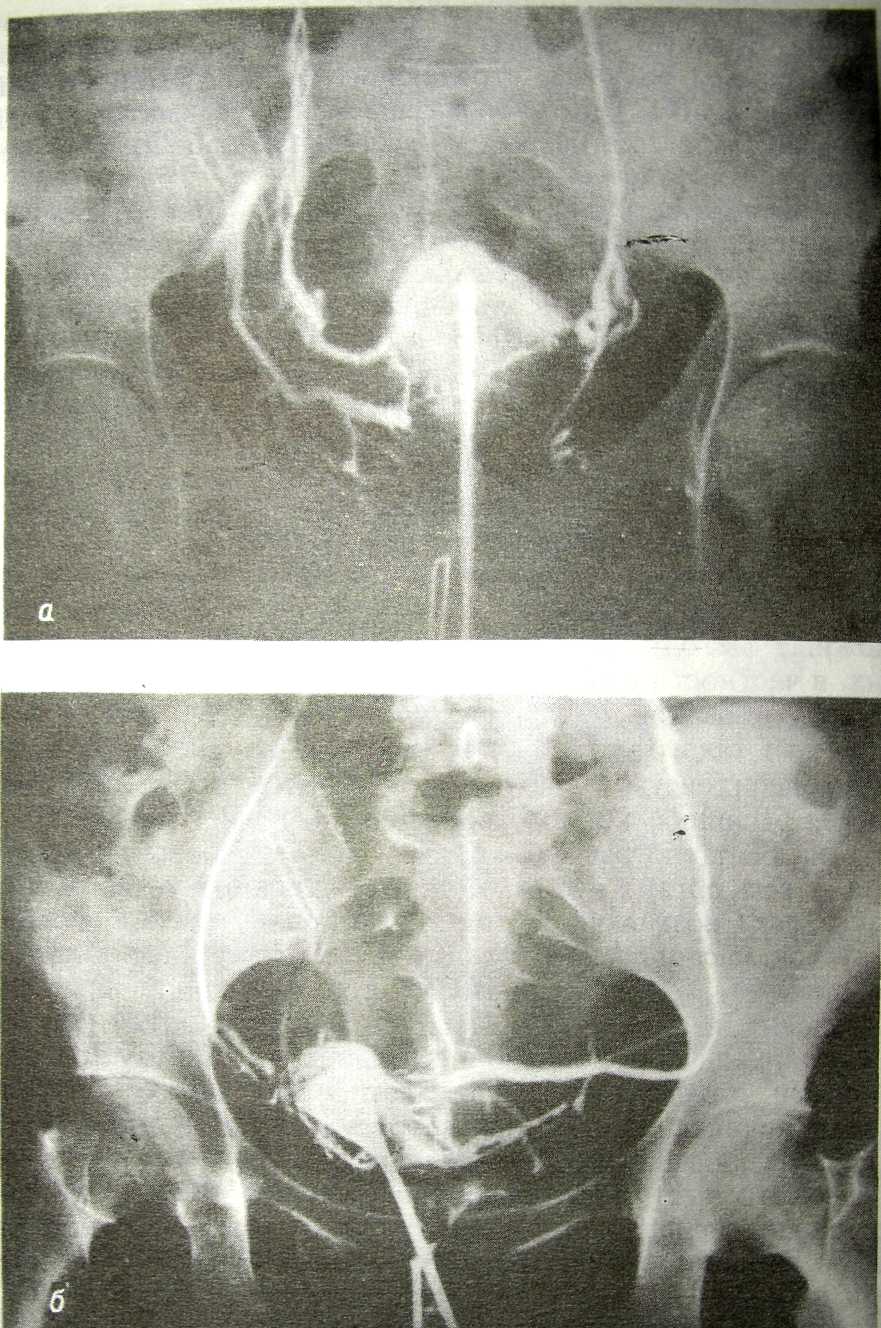

Гистеросальпингография: описание и фотографии